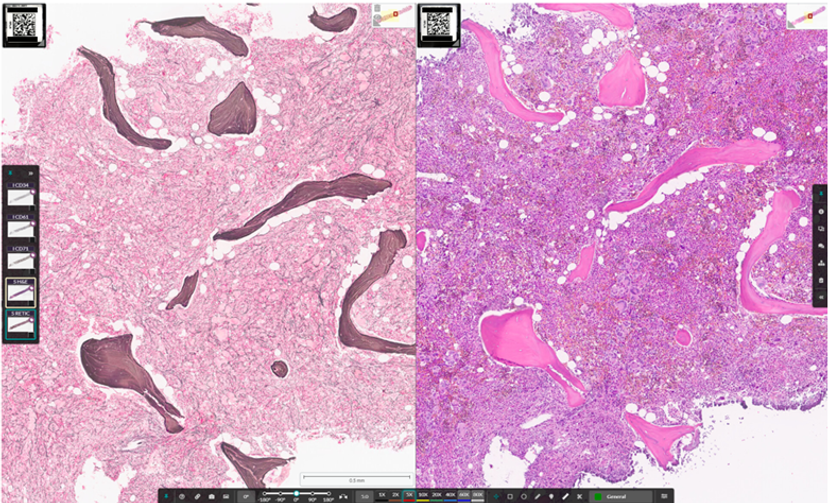

Myelofibrosis case with reticulin staining (left) and H&E (right)

Indica Labs has announced that Molecular Pathology Laboratory Network, Inc. (MPLN), a leader in laboratory medicine, hematopathology, and solid tumor oncology testing, has selected the HALO AP® platform from Indica Labs to deliver digital pathology services to both clinical reference labs and biopharma clients. HALO AP® is now in the final stages of clinical validation in MPLN’s CAP/CLIA-certified laboratory, where it is being prepared for initial deployment as a laboratory developed test (LDT) in the setting of urothelial bladder cancer and myeloid neoplasms. Additional disease indications will be validated in HALO AP® as LDTs in a stepwise manner once the initial indications are fully deployed.